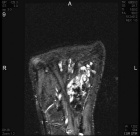

Patient is a 15 y/o male who presented c/o 9 month hx. of R. plantar foot pain w/ ambulation and palpable mass

Physical exam: there is a palpable 7x3 cm mass over the med-plantar aspect of R. foot; + tenderness to palpation; NVI

Zoom image: Radiological image Radiological image.